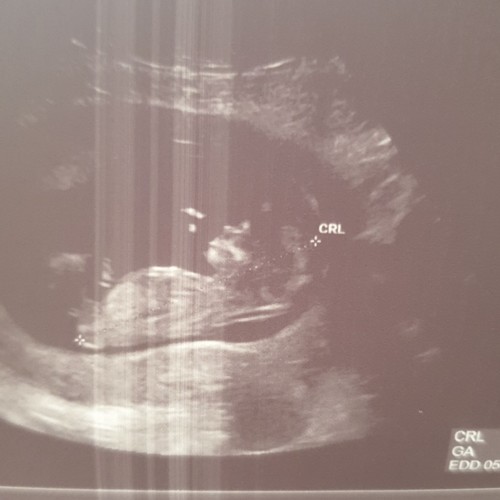

Afgaand op de NUB theorie is mijne een meisje denk ik?

Hoeveel weken ben je op deze echo?

11+2 en de verloskundige zei dat ze het zag maar volgensmij is het echt te vroeg

Ahh oké. De nub kun je eigenlijk pas met 12 weken echt inschatten. De verlo ...

Ze zei een meisje